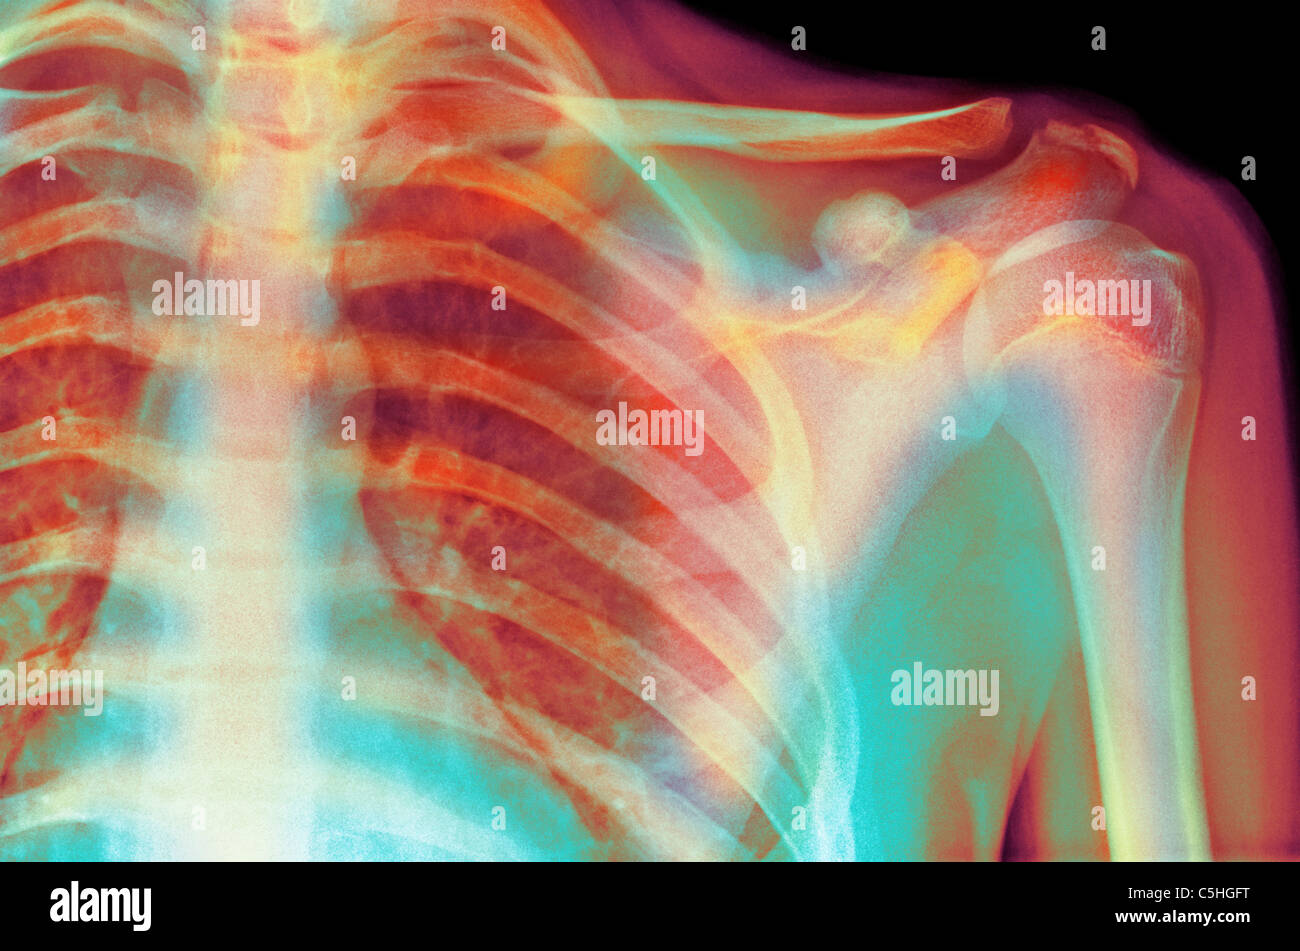

From www.alamy.com

Normal shoulder. Xray of the healthy left shoulder of a 28 year old What Does A Normal Shoulder X Ray Look Like As you've already seen, this isn't the. Ideally, a shoulder radiograph series will provide adequate views of the clavicle, acromioclavicular joint (acj), glenohumeral. A normal shoulder x ray will demonstrate the bones of the shoulder to have expected normal appearance without breaks,. A video tutorial in interpreting radiographs of the shoulder joint and surrounding areas. What Does A Normal Shoulder X Ray Look Like.